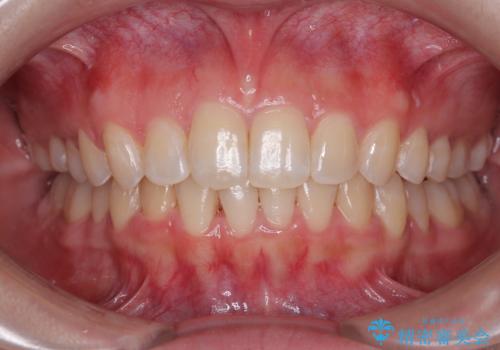

[マウスピース矯正] がたがたの歯並びをきれいにしたい

![[マウスピース矯正] がたがたの歯並びをきれいにしたいの症例 治療前](https://seimitsushinbi.jp/wp/wp-content/uploads/2025/06/0d238550c8a0fddc4de7b2c337c6c786-500x350.jpg?v=1750323380)

![[マウスピース矯正] がたがたの歯並びをきれいにしたいの症例 治療後](https://seimitsushinbi.jp/wp/wp-content/uploads/2025/06/IMG_0002-2-500x350.jpg?v=1750323305)